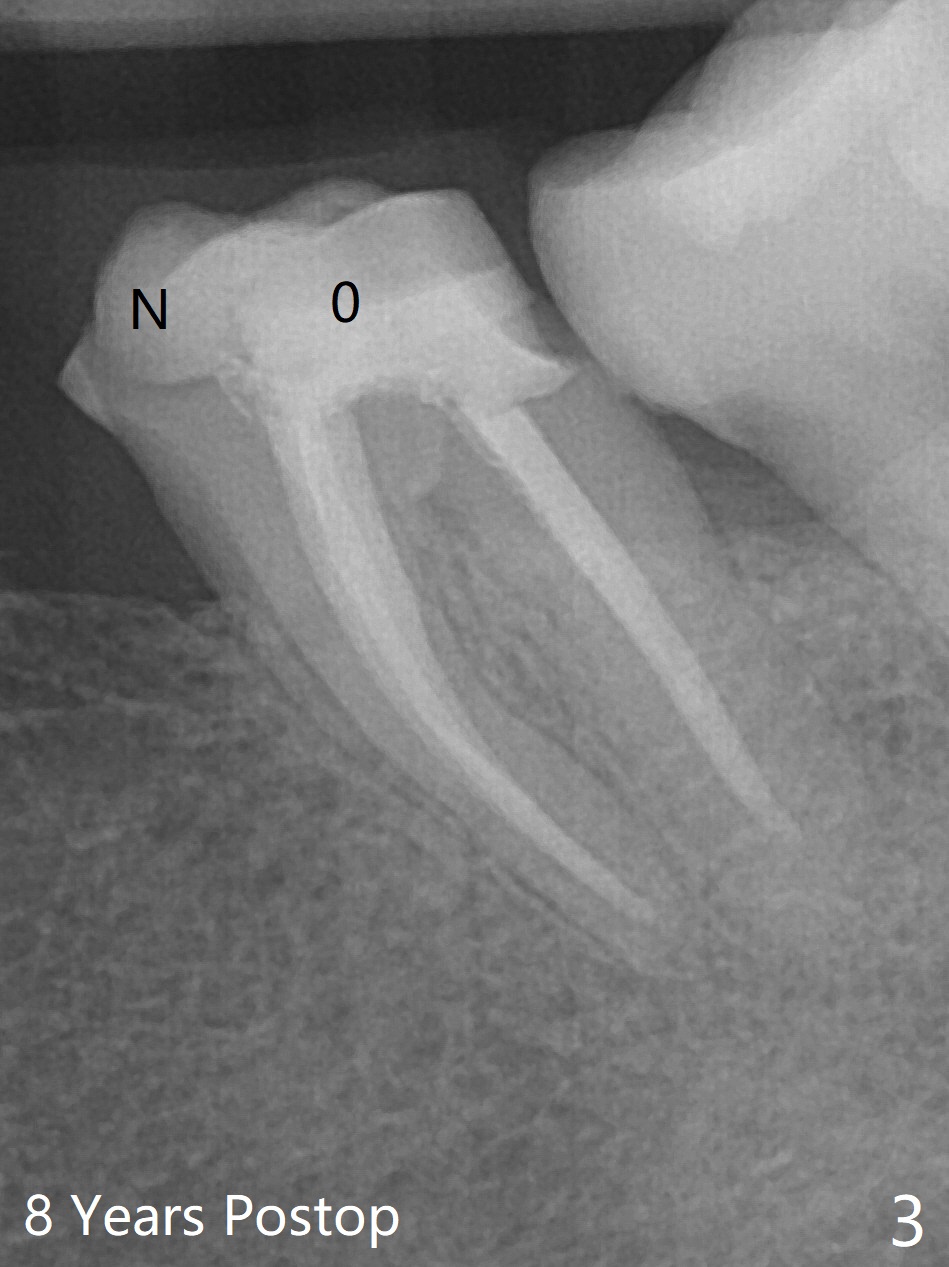

A 54-year-old woman, a dental phobic with RCT at #18 eight years ago (Fig.1,2), returns to clinic because of 2nd caries. New composite build-up is done around the old one before impression (Fig.3 N, O). BW will be taken before and after cementation for confirmation of marginal seal. How long will the crown of the tilted tooth last, as opposing to implants?